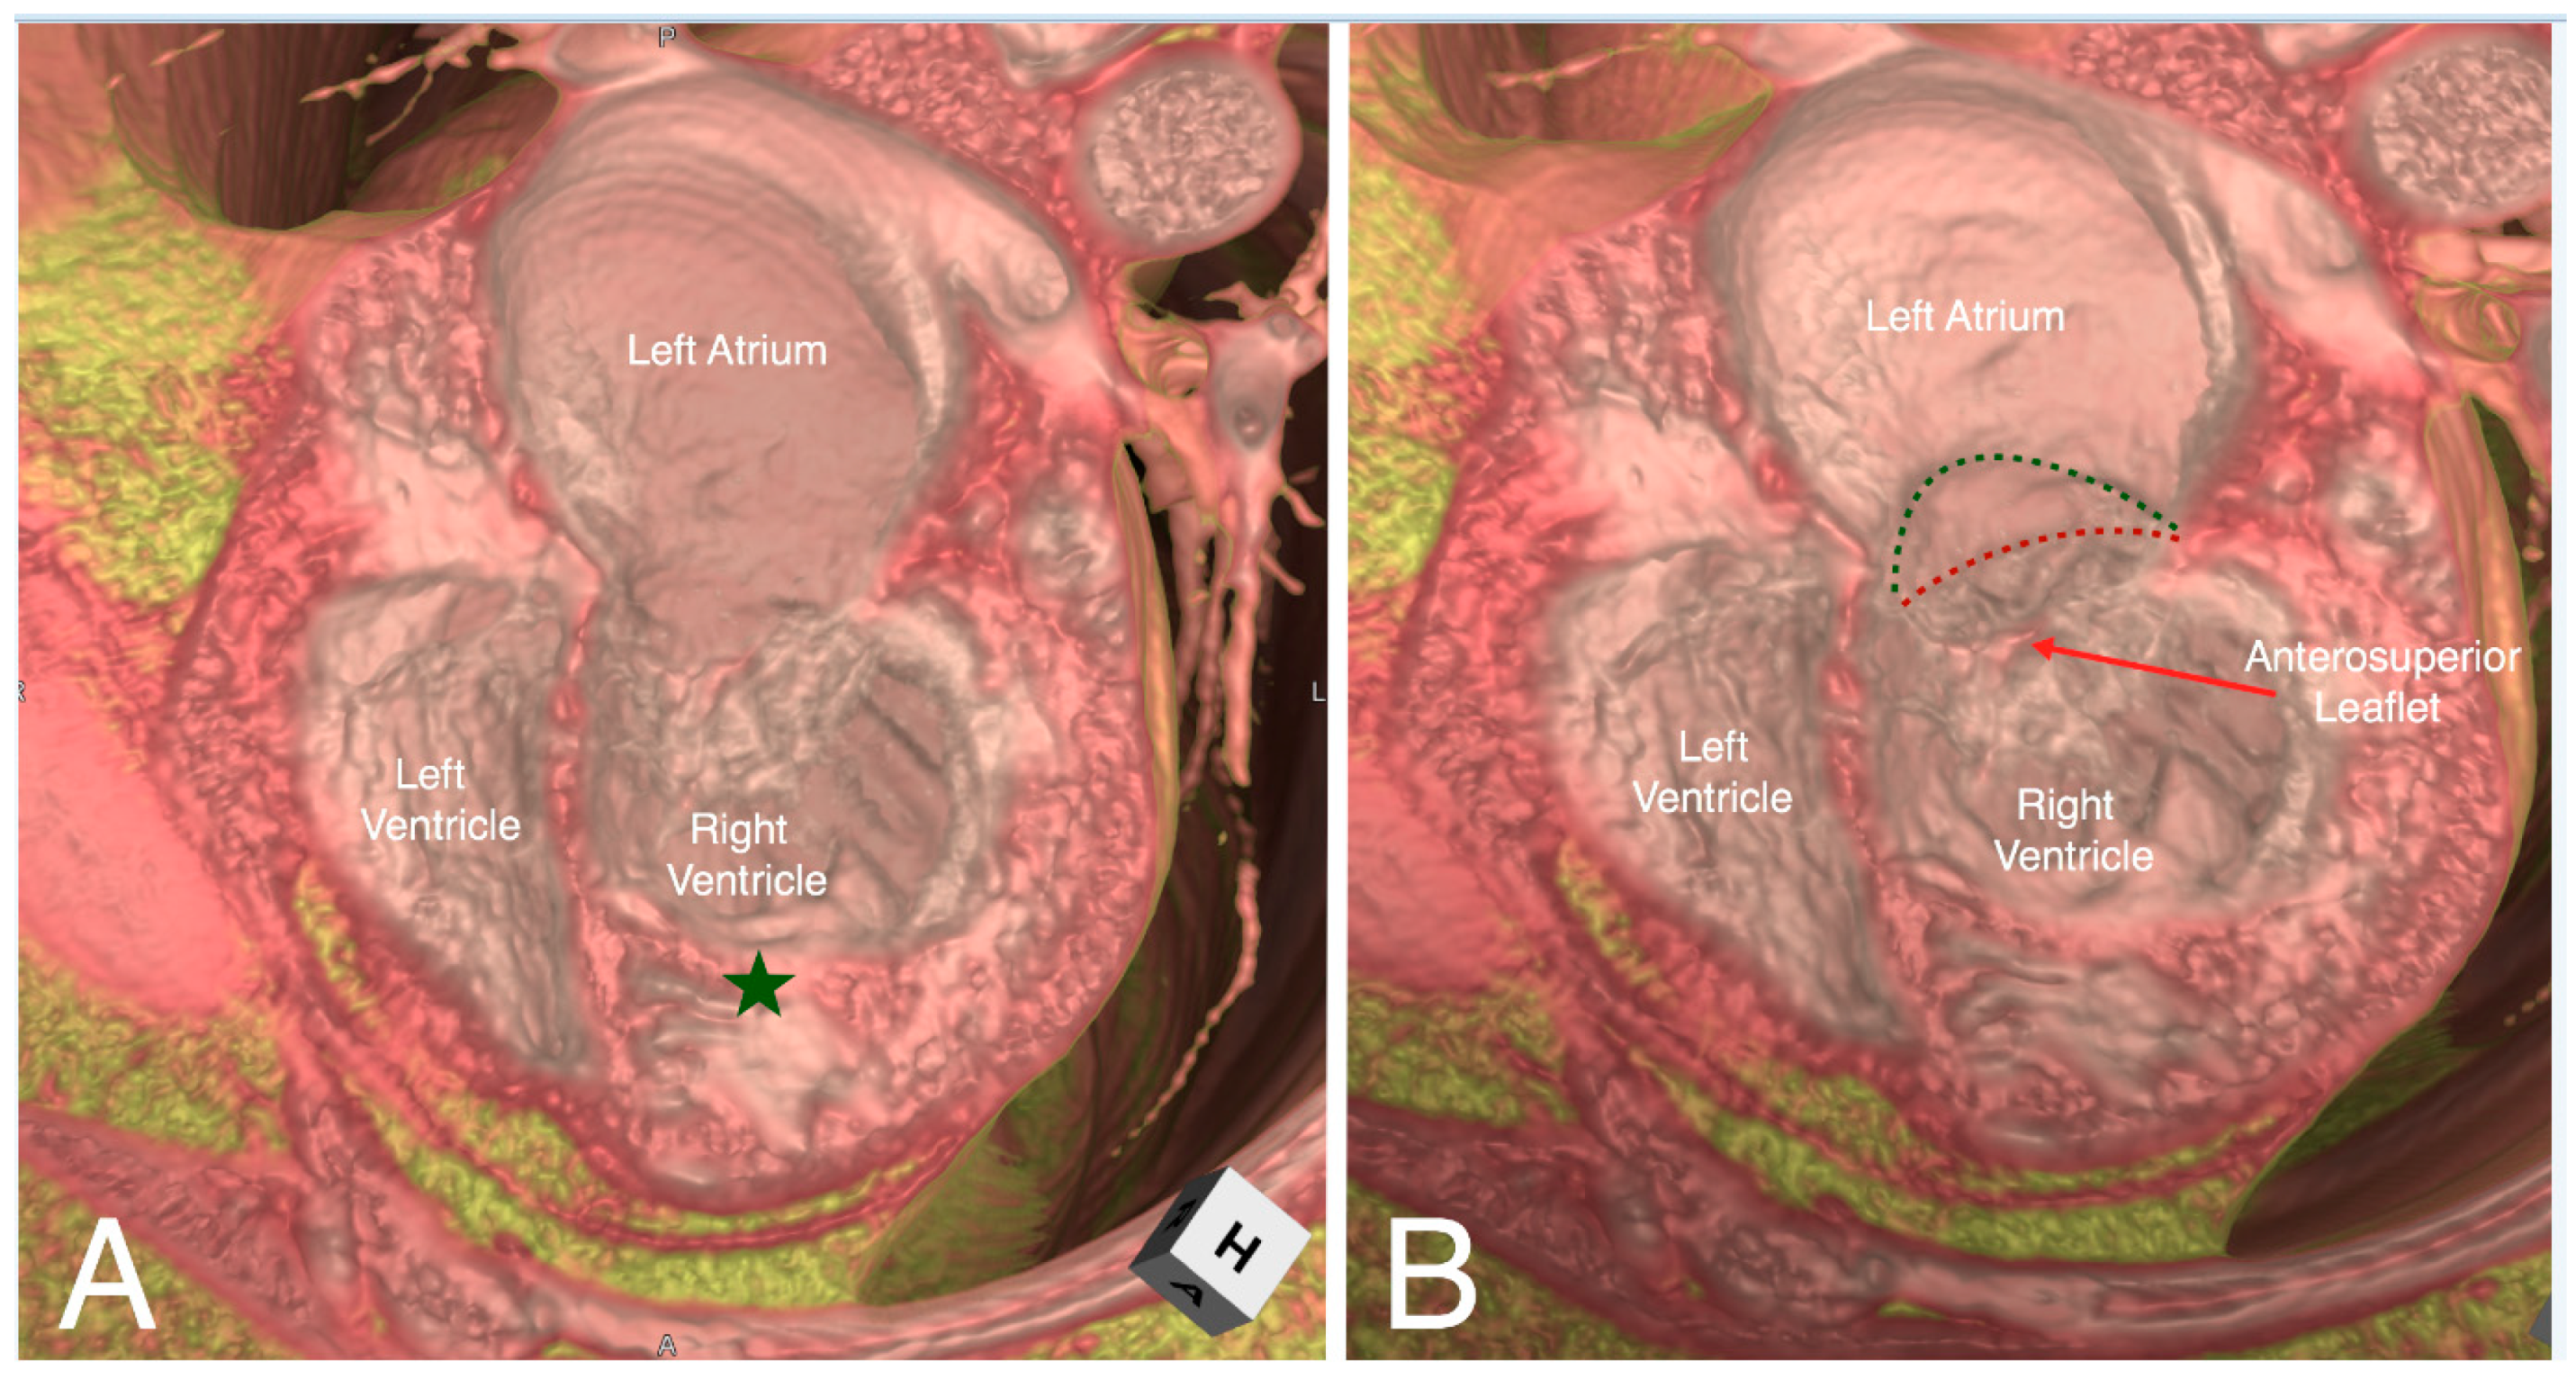

4. Educational Implication of the Three-Dimensional Living Heart Anatomy

5. Clinical Implication in Acquired Heart Disease with Representative Cases

6. Clinical Implication in Congenital Heart Disease with Representative Cases